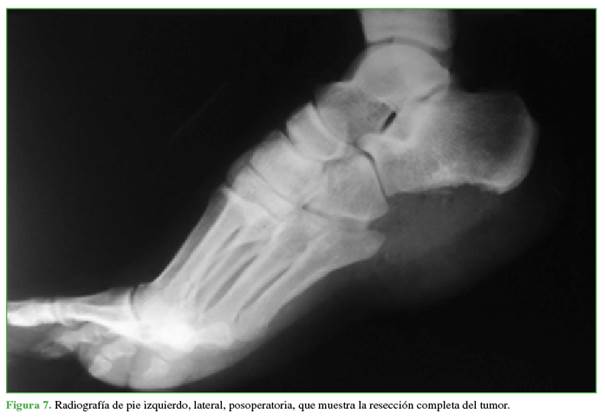

El período posoperatorio del paciente fue bueno, y las radiografías constataron la extracción completa del tumor (Figura 7).